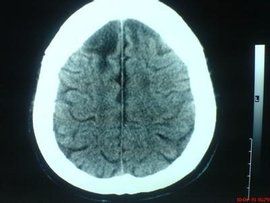

腦軟化3.恢復期 病變區往往呈現凹陷狀,較大者常為囊腫樣,囊壁可能光滑,含清亮或混濁液體,亦可能為縱橫、粗細不一的纖維囊束所橫跨形成多房狀。小者則為腔隙狀。更小者可能為較硬的瘢痕組織。

動脈粥樣硬化的病人,往往出現短暫性腦缺血發作,表現為一過性單肢癱或偏癱、肢體感覺障礙或失語等,24h內完全恢復。過去臨床醫生認為系腦血管痙攣所致,但硬化的動脈不易發生痙攣,故這種解釋已不為人們接受。根據細緻的臨床觀察,加之CT的問世以及屍檢工作的不斷探索,現在認為,這種短暫的發作,一部分由於細小栓子暫時阻塞了某一小動脈,引起功能障礙,但尚未引起組織的壞死,栓子即已脫落。正如作者曾遇一患者,左眼突然失明,檢查時發現左眼底小動脈內的玻璃樣栓子,數小時後,患者恢復了視力,眼底完全正常。另一部分,可能由於小的軟化灶形成,但離重要結構如內囊或上升性感覺纖維較遠,壓迫這些纖維所造成的輕微水腫幾小時即消失,故功能完全恢復,但軟化灶仍然存在。近來CT的套用對解釋該現象有很大幫助。如一患者病史中出現一次偏癱,但CT可能發現有3處軟化灶,說明其餘兩處並未造成症狀。有時患者從未有過卒中發作,而CT可發現2或3個軟化灶。屍檢工作者實際早注意到某些患者因一次卒中而亡,但腦內可發現另外兩個陳舊性軟化灶。說明這些靜區的病灶,若接近重要的結構,可能因水腫波及而使患者出現短暫的發作,證明許多所謂短暫性腦缺血發作並非沒有病理基礎。另一種所謂可逆性缺血性神經系統功能缺損,系神經系統功能障礙如單癱、感覺障礙、失語等,在3周內完全恢復。其症狀都是由於接近重要結構的軟化而引起。作者遇到一例患者,突然出現左側偏癱,3周完全恢復,但CT發現右側殼核有一軟化灶,這進一步說明所謂短暫的可逆性的病例,實際都是由軟化灶引起,有其病理基礎。只要臨床醫生理解發病機制,這些術語還可以保留,並有益於病人心理上的安慰。1993年Fries等報告了患者內囊後肢軟化後尚能完全恢復。他用磁共振檢查發現,內囊後肢確有軟化。這又有力說明大腦有著完備的代償功能。